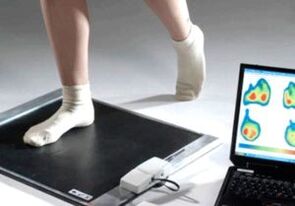

Si l'examen visuel et les radiographies ne donnent aucun résultat, le patient est référé à une plantographie pour déterminer d'éventuels pieds plats. Cette méthode consiste à prendre des empreintes de pas, à partir desquelles sont fabriquées des chaussures ou des semelles aux propriétés orthopédiques pour le patient. Le patient se voit alors prescrire une pédométrie. Cette méthode utilise une analyse informatique pour déterminer la pression du poids d'une personne sur ses pieds. Les résultats des diagnostics avancés constituent la base du choix d'une méthode de traitement de la courbure du premier et du deuxième doigt.

C'est la meilleure méthode de diagnostic informative. Avec son aide, le médecin détermine non seulement la présence de pieds plats, mais également l'état de la voûte plantaire. L’examen informatique est le moyen le plus efficace de détecter les pieds plats.